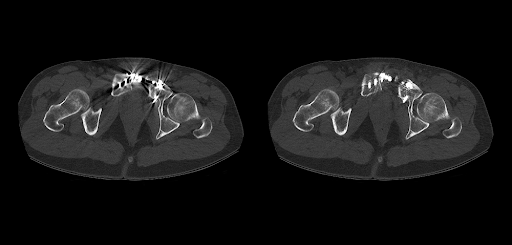

Автоматизированный выбор кВ в зависимости от размеров пациента – для уменьшенного количества контраста и более безопасного для почек сканирования. Технология SEMAR убирает артефакты, вызванные наличием металлических имплантатов, и повышает распознавание анатомических тканей вокруг них.КТ сканирования для кардиологии – с технологией SURE Cardio адаптирует параметры сканирования и экспозиции к каждому пациенту в режиме реального времени на основе тысяч клинических случаев. Доступно проспективное спиральное сканирование сердца с низкой лучевой нагрузкой.

Технология SEMAR позволяет снизить количество артефактов от металла, что является важным инструментом при исследовании позвоночника.